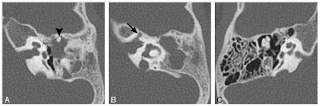

Şekil 1: Michel Labirent aplazisi. Aksiyel (A) ve koronal (B) kesitlerde normal iç kulak yapıları bulunmamaktadır. İyi gelişmiş bir iç kulak kanalının olmayışı, tabloyu labirentitis ossifikans olgusundan ayırmaktadır.

Şekil 2: İnkomplet partitisyon II (Mondini aplazisi). Modiolus yokluğu ve kohlear apeks ile orta kanalın birleşiminden oluşan büllöz apeks görünümü. Vestibül ve YDK normal, vestibüler aquadukt geniş değil.

Bu sınıflamada Michel aplazisi "Total Kohlea ve Vestibül Aplazisi" olarak tanımlanır (Şekil 1). Gebeliğin 3-4.haftalarındaki etkilenmeler vestibül vardır ve "Kohlear Aplazi" olarak tanımlanmıştır (Şekil 3).

Şekil 3: Kohlear aplazi. Vestibül displastik olup lateral kanal ile anormal bir birleşme göstermekte. Vestibüler sinir kanalı daralmış (ok).

Gebeliğin 4.haftasındaki etkilenmelerde kohlea ve vestibül ayırımı olmaksızın tek bir boşluk halinde gelişimle karşılaşılır ve "Common Cavity" olarak adlandırılır (şekil 4). Gebeliğin 5.haftasındaki etkilenmelere bağlı kistik kohleavestibüler malformasyon (Incomplate partitation-I) oluşur ki, modiolus ve kribriform bölge gelişmemiştir ve kohlea ile vestibülde kistik gelişim görülür (Şekil 5).

Şekil 4: Common Cavity deformitesi. Aksiyel (A) ve rekonstruktif (B) görüntülerde kohla ve vestibül tek bir boşluk halinde olup, farklılaşmaları gelişmemiştir.

Şekil 5: İnkomplet partitisyonda kohlea ve vestibül birbirinden tam ayrılamamış ancak ayrılma prosesi başlamıştır. Böylece kohlear ve vestibüler kaviteler bir arada kistik bir formasyonla "8" figürü veya "Kardan Adam" manzarası oluşturur.

Gebeleğin 6.haftasındaki etkilenmeler sonucunda kohlear hipoplazi oluşur. Kohlea ve vestibül kısmen ayrılmıştır ancak kohlea çok küçük yapıda olup, interenal akustik kanalın ucunda bir tomurcuk gibi görülür (Şekil 6). Gebeliğin 7. haftasında oluşan etkilenmelerde kohlea gelişimini yaklaşık 1,5 tur olarak gerçekleştirebilir, apeks ve ikinci döngüsü bir arada olup, kistik bir görünüm sergiler (Şekil 2).

Şekil 6: Kohlear hipoplazi. Kohlea internal akustik kanalın ucunda tomurcuk gjbi gürünür, Vestibül geniş ve diplastiktir, LSK ile cep şeklinde birleşmiştir.